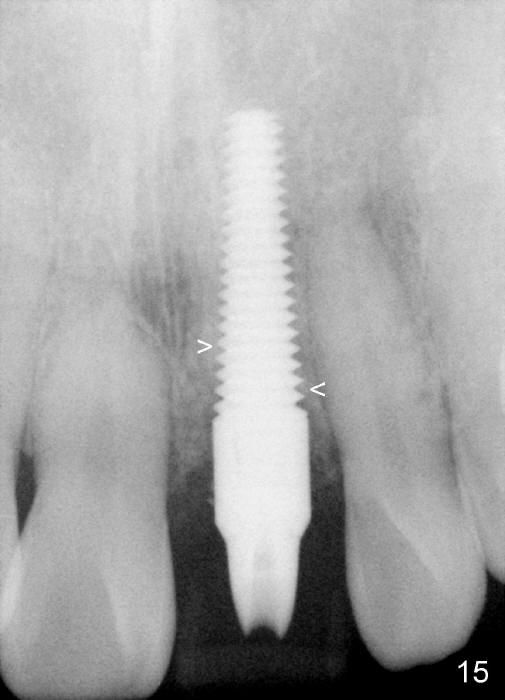

Bone expansion allows the implant (Fig.9 I) to have primary stability (insertion torque between 50 and 60 Ncm), since the cortex of the incisive canal is apparently intact.  Allograft is placed in the labial gap (Fig.10, 11 *) following installation of the abutment (A).  Finally an immediate provisional (Fig.10,12 P) is cemented.  Fig.13,14 are taken 8 days postop.  The patient returns 3 months postop (Fig.15,16).  Osteointegration appears to have occurred (Fig.15 arrowheads) and is more obvious 9 months postop (Fig.17).